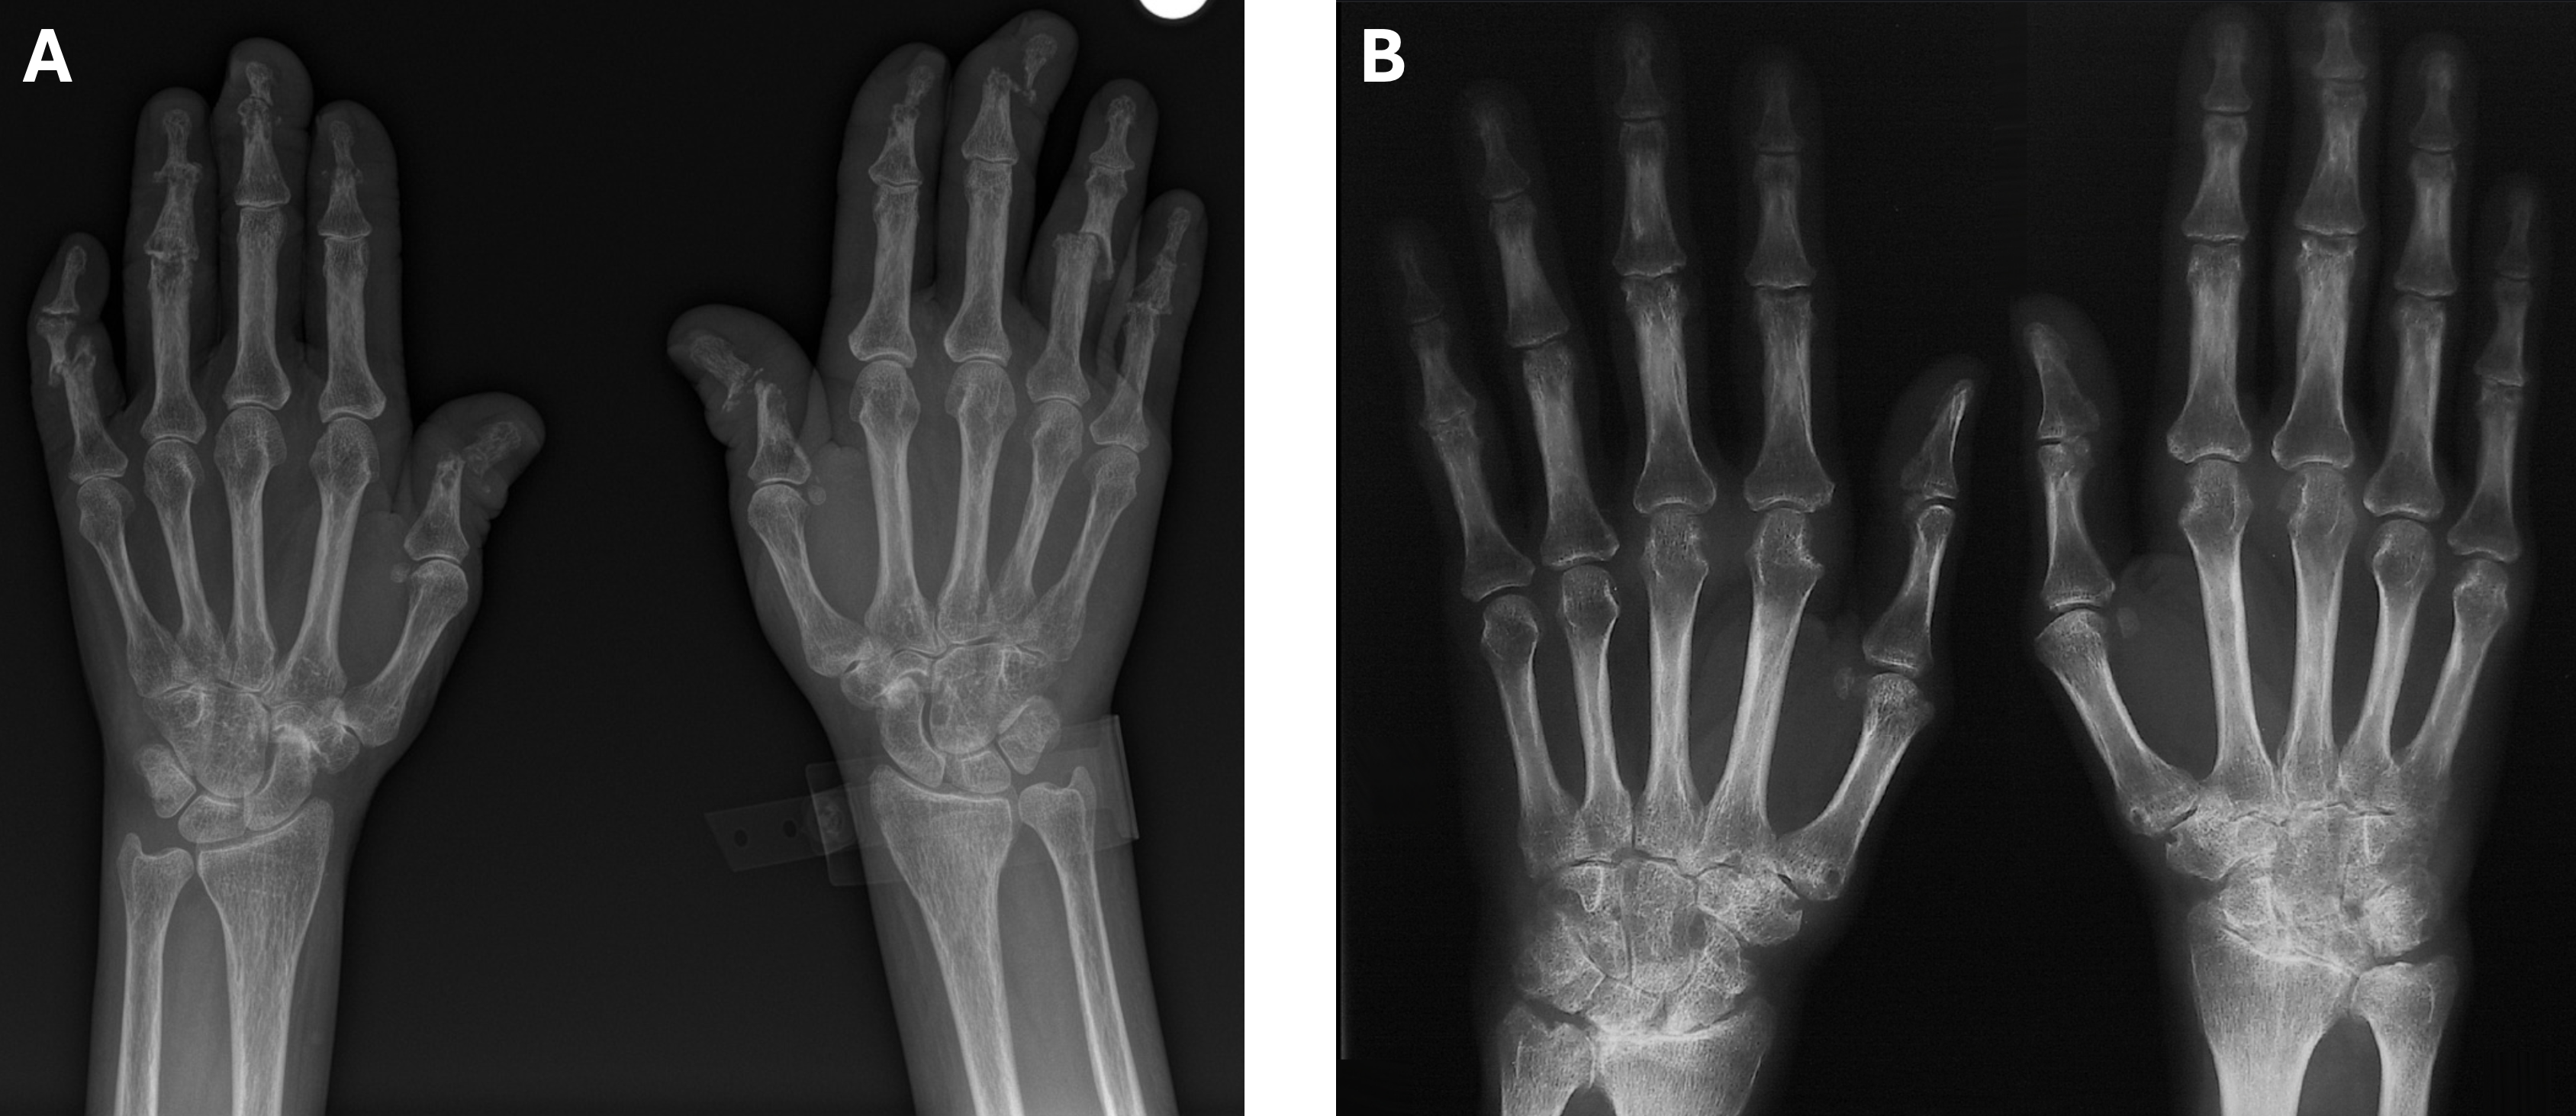

Sie sehen zwei Röntgenbilder der Hände. Welchen Fall würden Sie aufgrund des Verteilungsmuster der ossären Veränderungen eher einer Rheumatoide Arthritis und welchen eher einer Psorias Arthritis zuordnen?